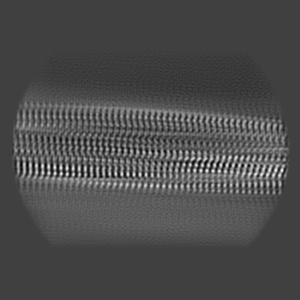

Structure of pathological TDP-43 filaments from ALS with FTLD

Sample: Pathological TDP-43 filaments extracted from the frontal cortex of an individual that succumbed to ALS with FTLD.

Structure of pathological TDP-43 filaments from ALS with FTLD.

Arseni D , Hasegawa M , Murzin AG, Kametani F , Arai M , Yoshida M, Ryskeldi-Falcon B

(2022) Nature , 601 , 139 - 143